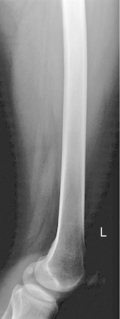

• Supine, femur centered to midline of table or grid IR

• Rotate entire lower limb internally ≈5° for AP of midfemur and distal femur, and 15° internally for true AP to include hip.

• Lower border of IR ≈5 cm (2″) below knee to include knee joint adequately (see AP Unilateral Hip for proximal femur, p. 156).